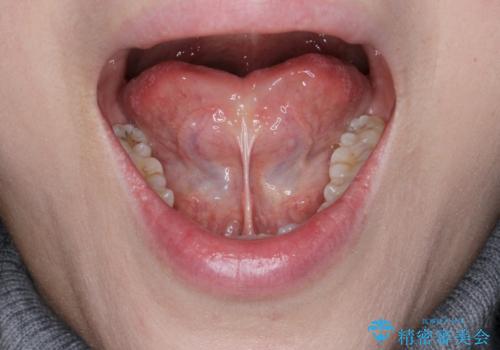

滑舌を改善したい 舌小帯の形成術

- 長年気になっていた、滑舌の問題を改善すべく舌小帯の形成手術を希望され来院されました。

舌の小帯が長く、舌の動きを制限しているため手術により改善を計画します。